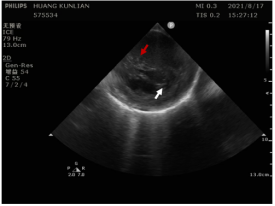

目标清晰,精准放电

在超声影像的指引下,确定导管与左后乳头肌的相对位置,进行精准放电消融,并在有效靶点附近进行巩固消融。

图片附件

消融导管在消融